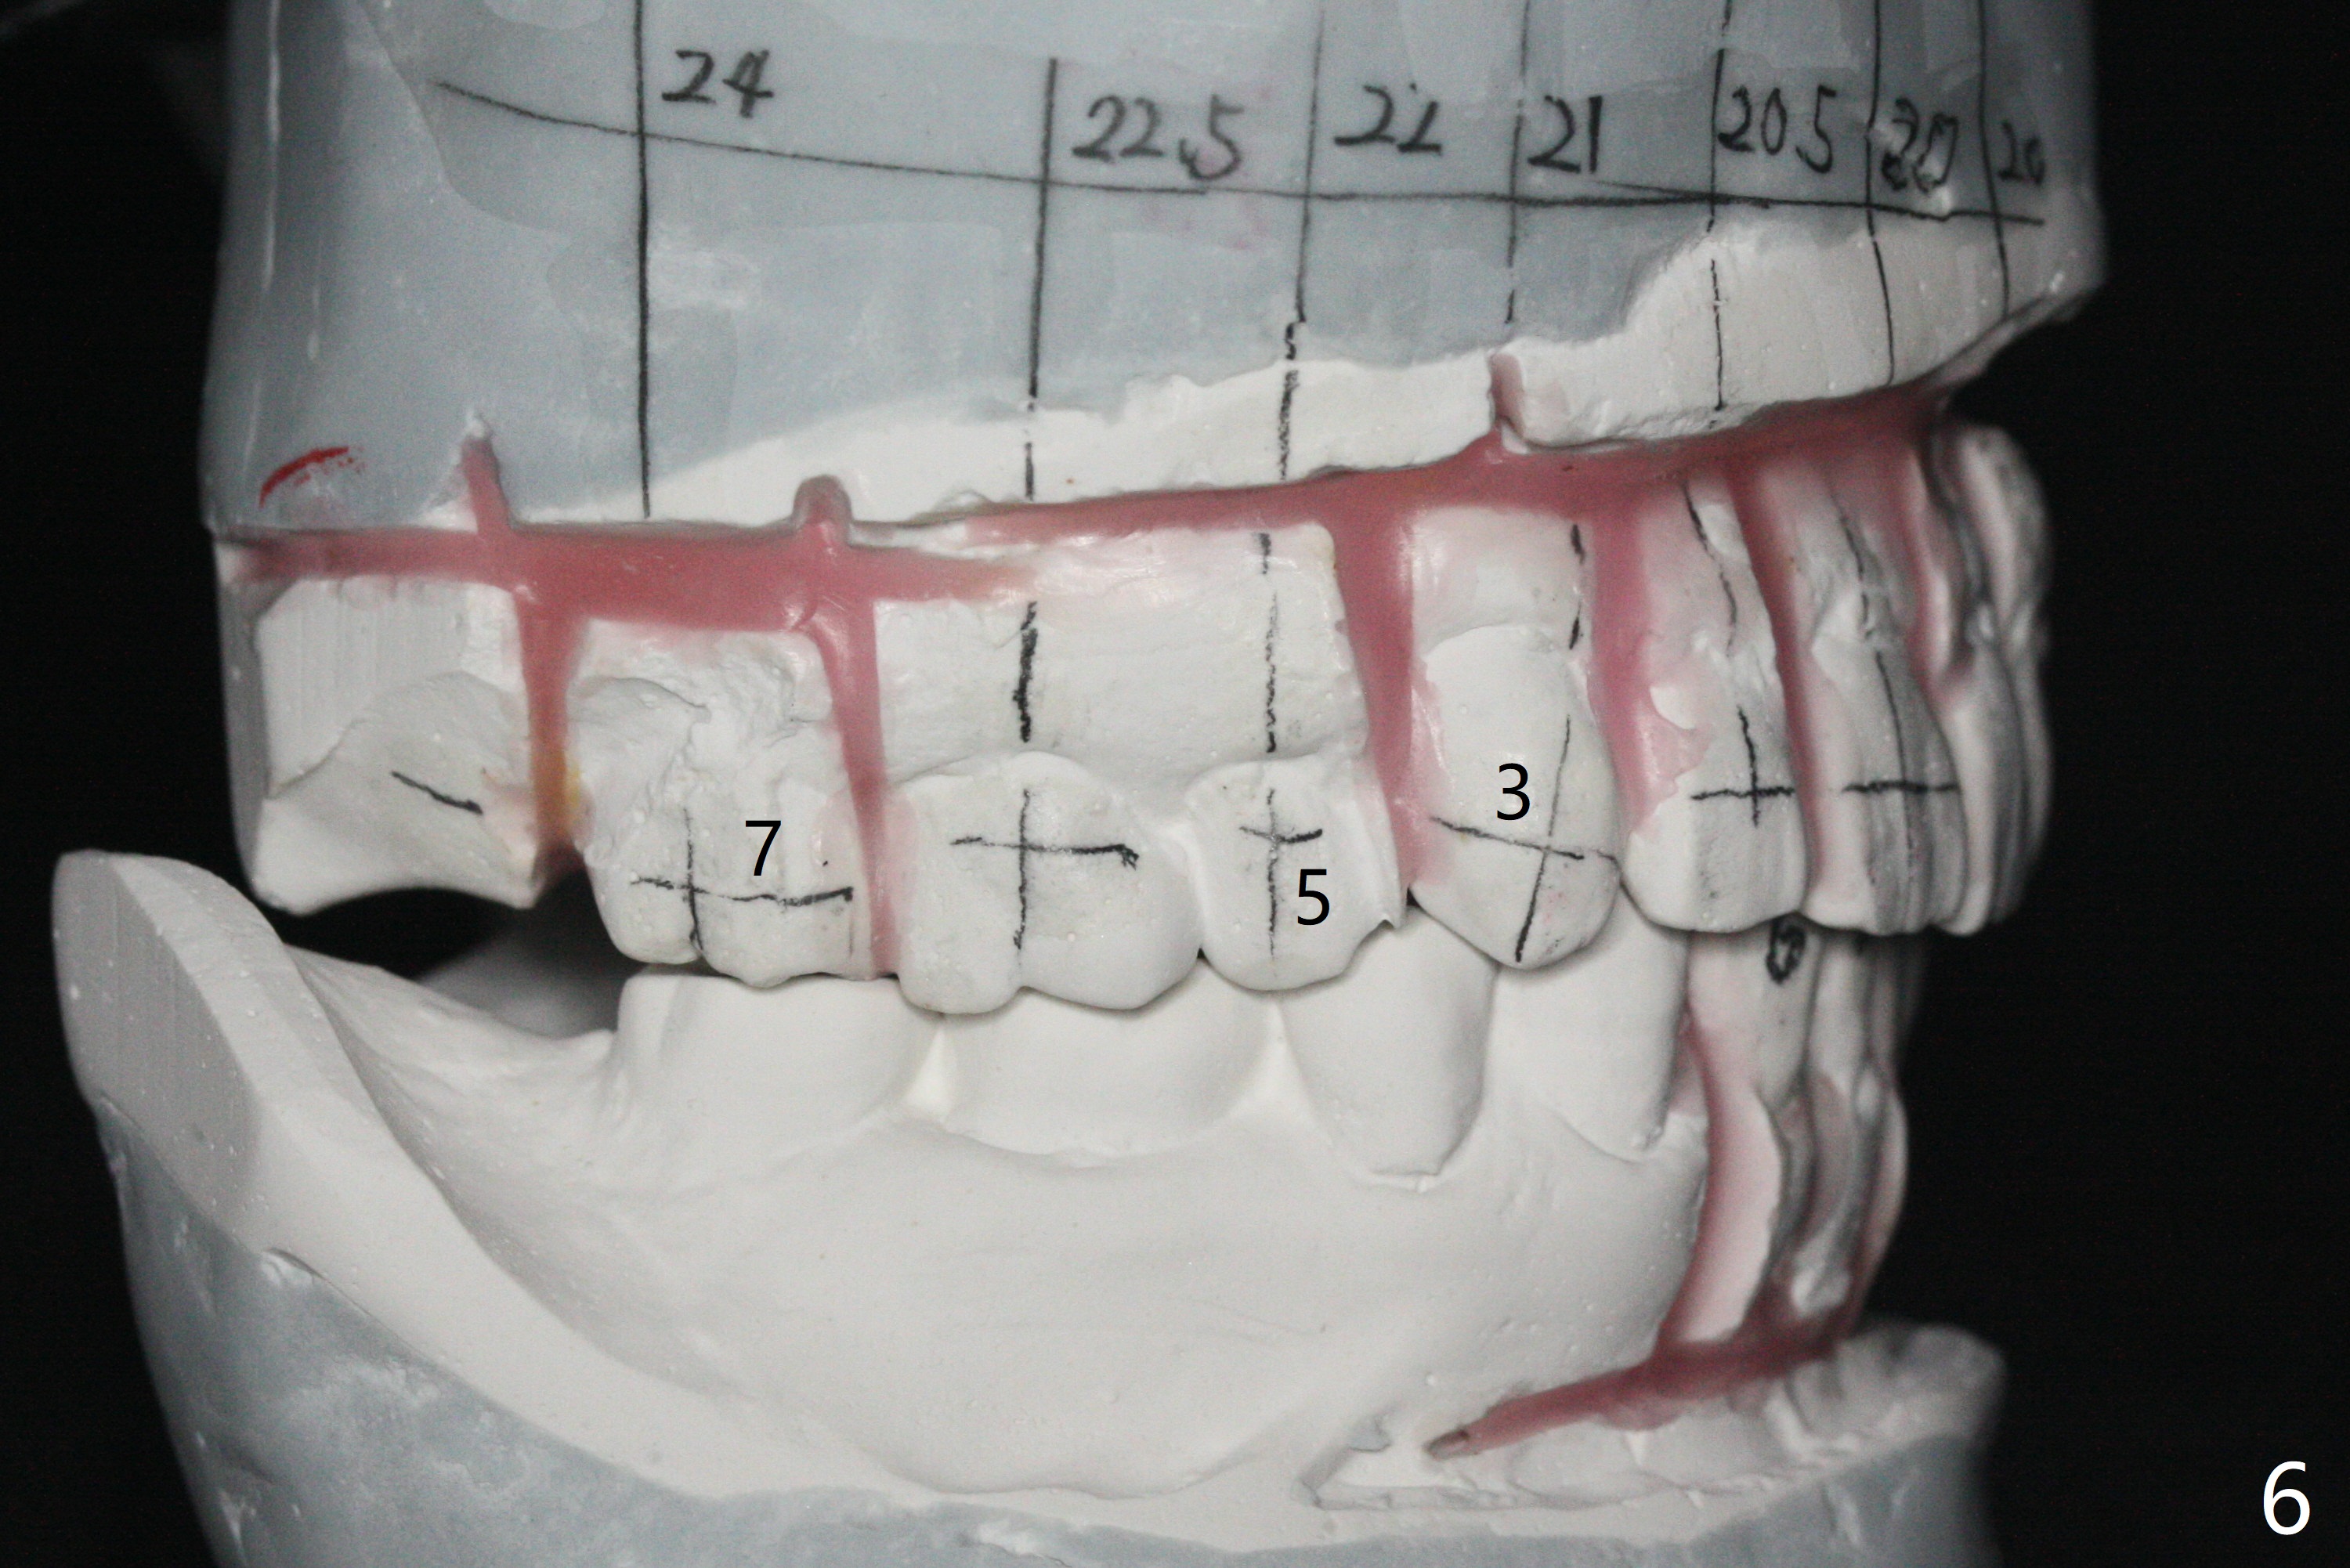

A 54-year-old man remains difficult in mastication in spite of implant placement at #14 and 31 (Fig. A, B, E, including screw loosening (poor trajectory at #14)). In addition to 2 more implants at #15 and 18 with guide, malocclusion seems to be necessary to be addressed (Fig.1-5). It appears that UR, LL4 should be extracted for orthodontic treatment (Fig.6-10). To reduce screw loosening, IS guide will be used to place IBS (5x9mm) and tissue-level (5x11mm) implants at #15 (PRF)and 18, respectively. If the one at #14 or 15 keeps loosening, splint #14 and 15 crowns. In fact the patient agrees with limited ortho (UR7 cross bite).